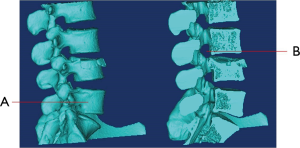

1. what’s name of bone that marked as “A”

- Spinous process

- Vertebral body

- Vertebral disc

- Sacrum

2. What’s name of the site marked as “B”?

- Transverse foramen

- Intervertebral space

- Pedicle

- Intervertebral foramen

3. Which vertebrae does the fracture involve?

- L3

- L4

- L5

- Both L4 and L5

4. Which following construct does the fracture involve?

- Vertebral body

- Vertebral body and pedicle

- Vertebral body, pedicle and lamina

- Vertebral body, pedicle, lamina and spinous Process

5. Which following construct impacted by the fracture?

- Intervertebral space

- Intervertebral space and vertebral foramen

- Intervertebral space, vertebral foramen and intervertebral foramen

- None of above.